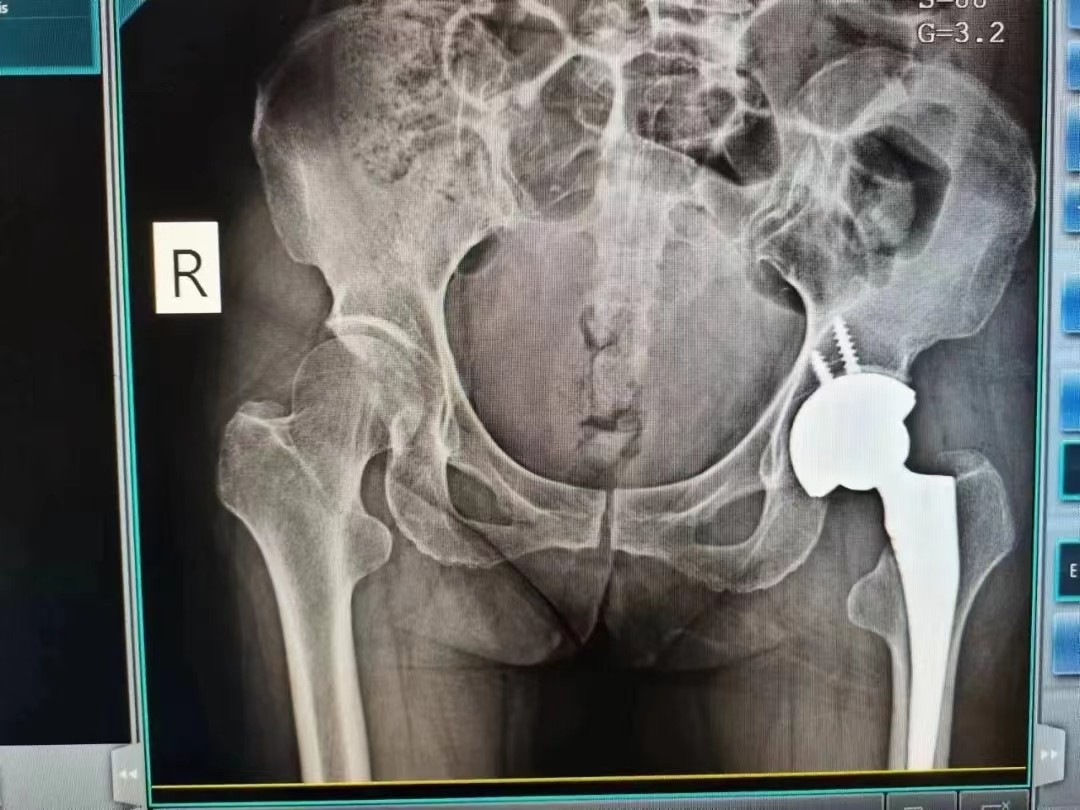

10月29日下午,程广东主任带领团队为应奶奶行左侧人工全髋关节置换术,手术过程顺利,历时较短,效果显著。

术后X线片

术后第二天在医生的指导下,应奶奶就能利用助行器下床进行患肢的功能锻炼,目前正在进一步康复中,估计术后一周就能痊愈出院了,此次的手术与治疗家属非常满意,连声称赞医务人员认真负责,服务细致。